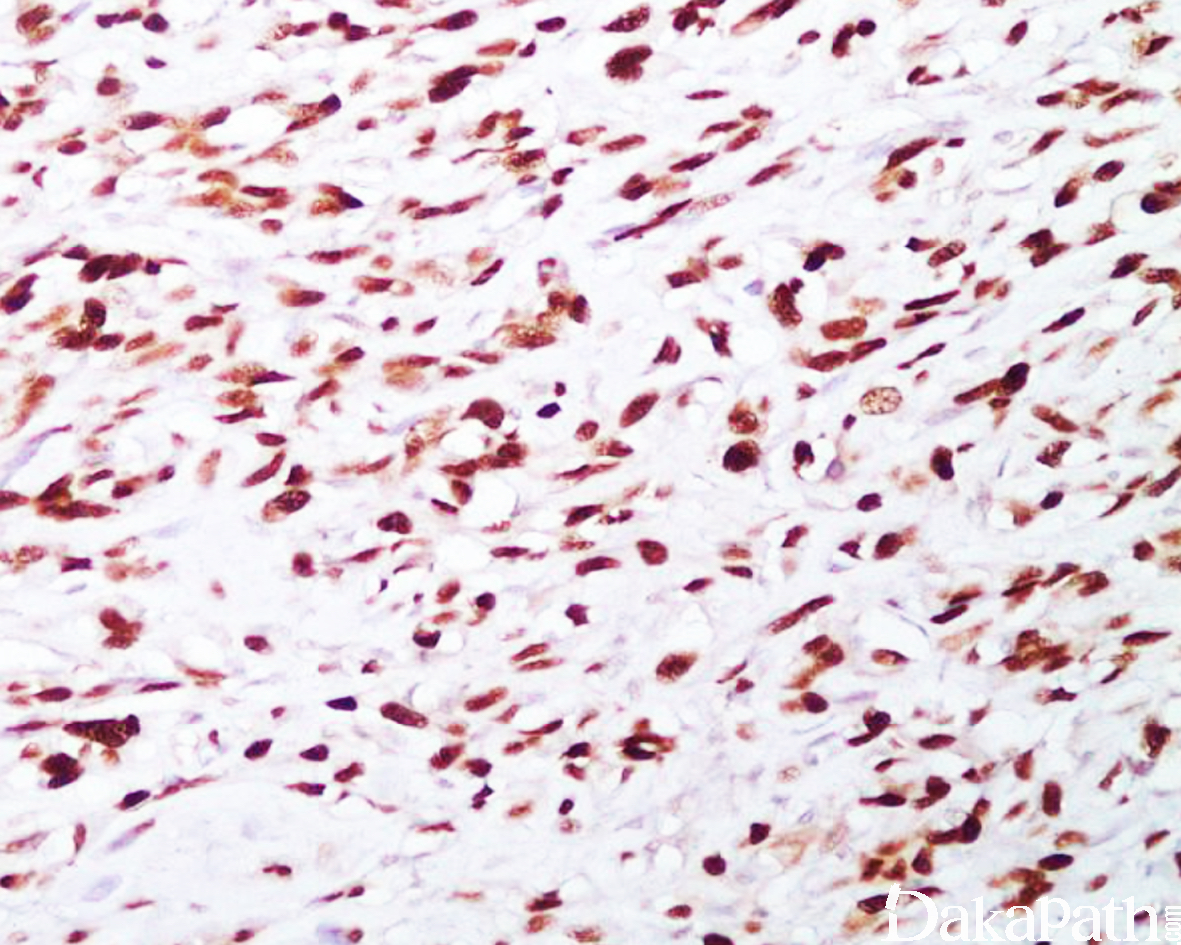

SATB2

信号定位: 胞核

1、小细胞骨肉瘤(90%骨肉瘤肿瘤细胞及骨样基质阳性,46%的软骨肉瘤阳性,仅 1.3%的尤文肉瘤阳性)的诊断;

2、 原发灶不明肿瘤的诊断,SATB2 阳性提示下消化道(75%结直肠及 80%以上的阑尾腺癌阳性,胰腺、胃、胆囊、卵巢、宫颈、宫内膜腺癌阴性)来源。